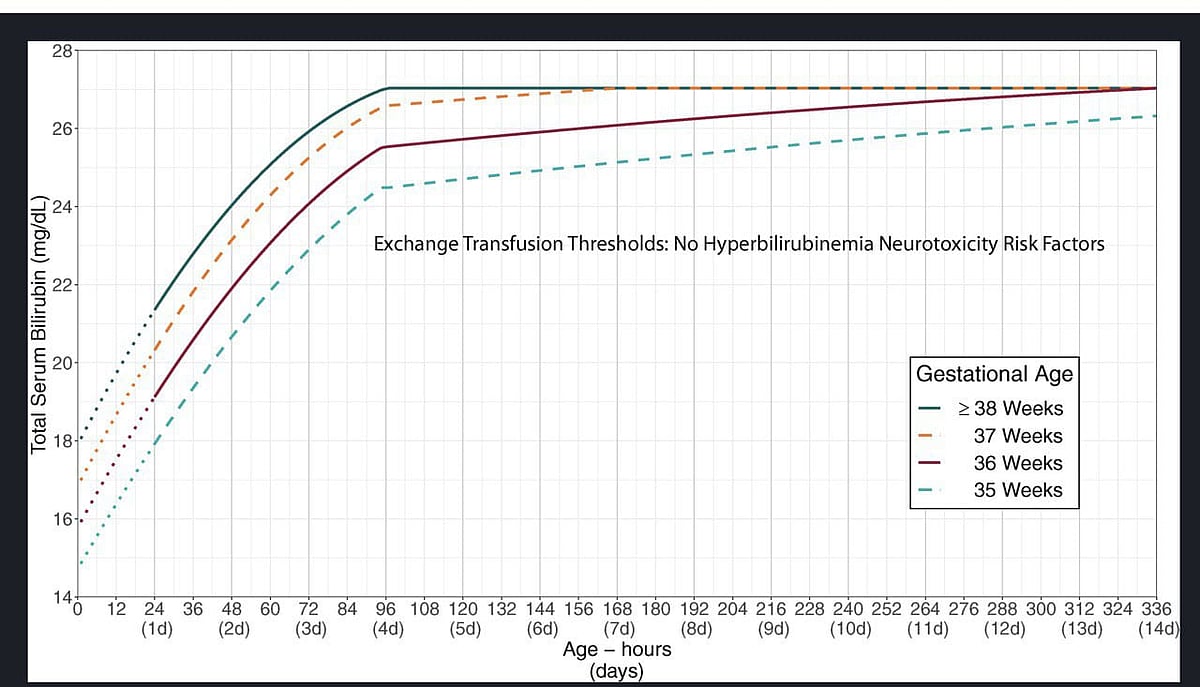

* பிலிருபினின் அளவு, ‘American Academy of Pediatrics (AAP)’-ன் ரத்த மாற்றம் வரைகட்டத்தில் நிர்ணயிக்கப்பட்டுள்ள பிலிருபின் அளவுகோலில் இருக்கும்போது.